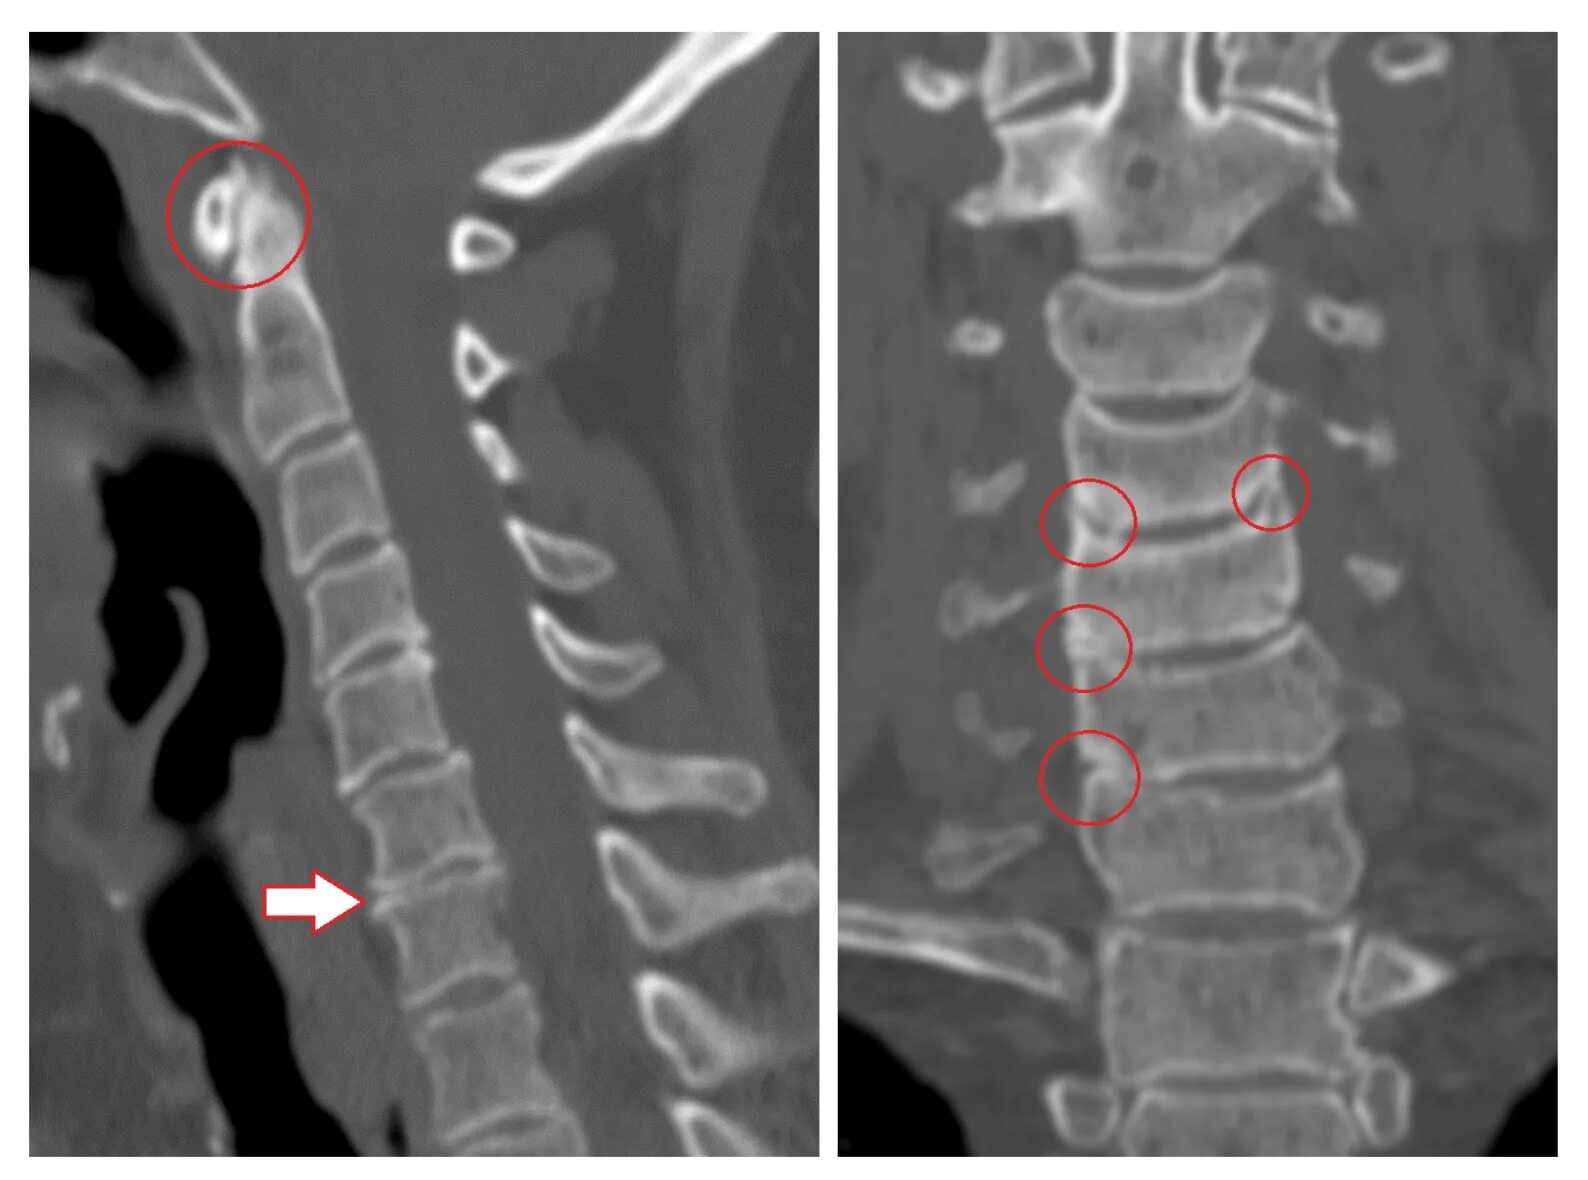

Спондилоартроз шейного позвоночника